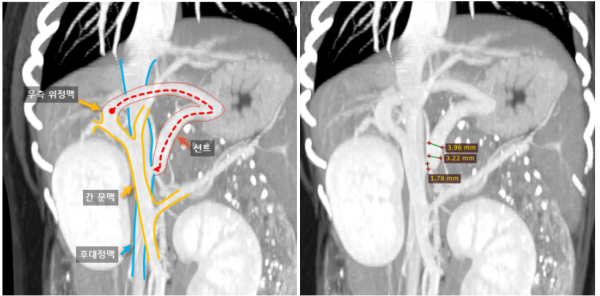

→ 혈액검사에서 암모니아, 담즙산, 간수치 상승을 보였습니다.

→ 영상진단에서는 소간증, 간외성 PSS 의심 소견이

나와 CT 진행 후 간문맥전신단락(PSS)를

진단하였습니다.

94e62ed5723a30503d8471b780ac418b_1759136028_0349.jpg

→ □□이에게 ameroid ring 결찰술과

간 생검을 진행했습니다.

5일간 입원 치료 후 퇴원하였으며,

간 생검 결과 HMD 소견이 나와

지속적인 관리가 필요하다는 안내를 드렸습니다.